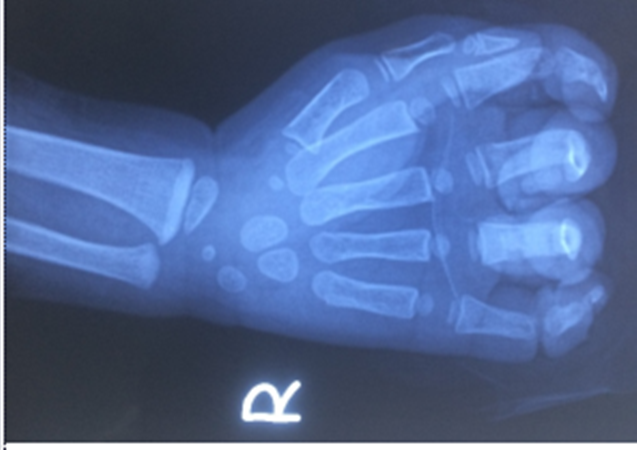

Hình ảnh phim chụp bàn tay bệnh nhi 23 tháng tuổi ở Vĩnh Phúc.

Gia đình cho biết, bé V bị kẹt tay vào dây coroa của máy rửa xe tại nhà. Sau khi được xử trí tại bệnh viện tỉnh, bé V. được chuyển lên Bệnh viện Hữu nghị Việt Đức vào 10h ngày 1/12 trong tình trạng vết thương mặt mu ngón từ 1-5, đứt gân duỗi 2 tầng ngón 2,3,4, đứt gần rời ngón 5 tại vị trí khớp liên đốt gần, bàn tay bé có nhiều vết bẩn dầu luyn.